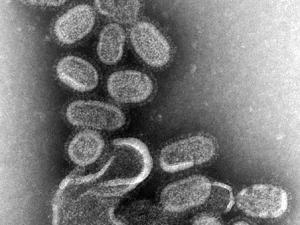

Bringing the deadly Spanish Flu to the 21st century can prevent pandemics. (Centers for Disease Control, Wikimedia Commons)

A deadly virus has been resurrected...for the benefit of public health?